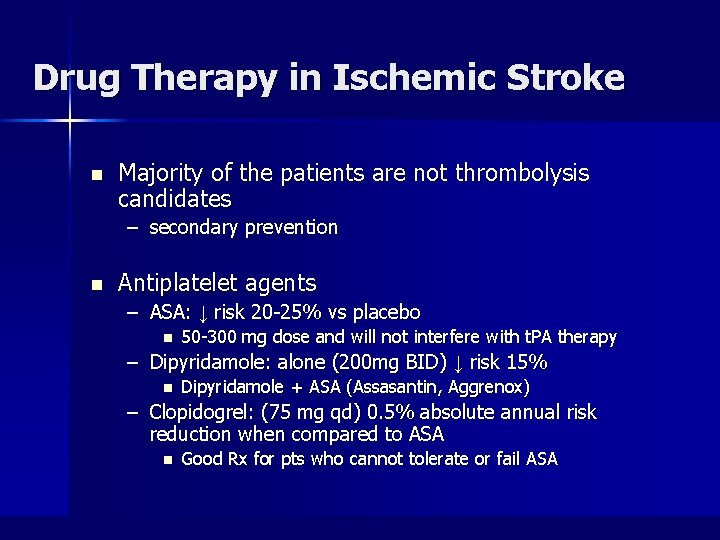

Drug Therapy in Ischemic Stroke n Majority of the patients are not thrombolysis candidates – secondary prevention n Antiplatelet agents – ASA: ↓ risk 20 -25% vs placebo n 50 -300 mg dose and will not interfere with t. PA therapy – Dipyridamole: alone (200 mg BID) ↓ risk 15% n Dipyridamole + ASA (Assasantin, Aggrenox) – Clopidogrel: (75 mg qd) 0. 5% absolute annual risk reduction when compared to ASA n Good Rx for pts who cannot tolerate or fail ASA